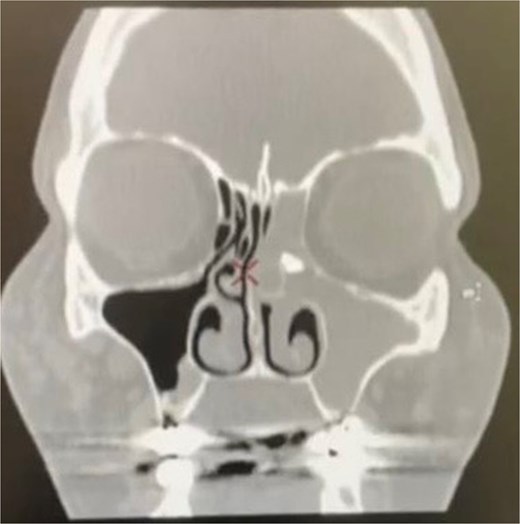

A 54-year-old woman with a history of extraction of the left maxillary molar tooth ⁓6 months prior visited our clinic with complaints of left nasal obstruction, green malodorous nasal discharge, hyposmia, and left-sided facial pressure for 3 months. She had been treated with multiple courses of oral antibiotics, intranasal corticosteroids, and saline nasal irrigation without improvement. The patient had a history of routine dental extraction performed by a general dentist. However, displacement of a root fragment was not documented. Nasal endoscopy on presentation revealed severe left middle meatus edema with thick pus discharge, and nasopharyngeal examination revealed post-nasal discharge. Examination of the ear, throat, neck, and cranial nerves revealed no significant findings. Computed tomography (CT) of the paranasal sinuses revealed a 10 × 6 mm radiopaque lesion in the left anterior ethmoid sinus with complete opacification of the left paranasal sinuses (Fig. 1).

Coronal computed tomography image showing left maxillary and ethmoid sinusitis and a foreign body in the left anterior ethmoid sinus.